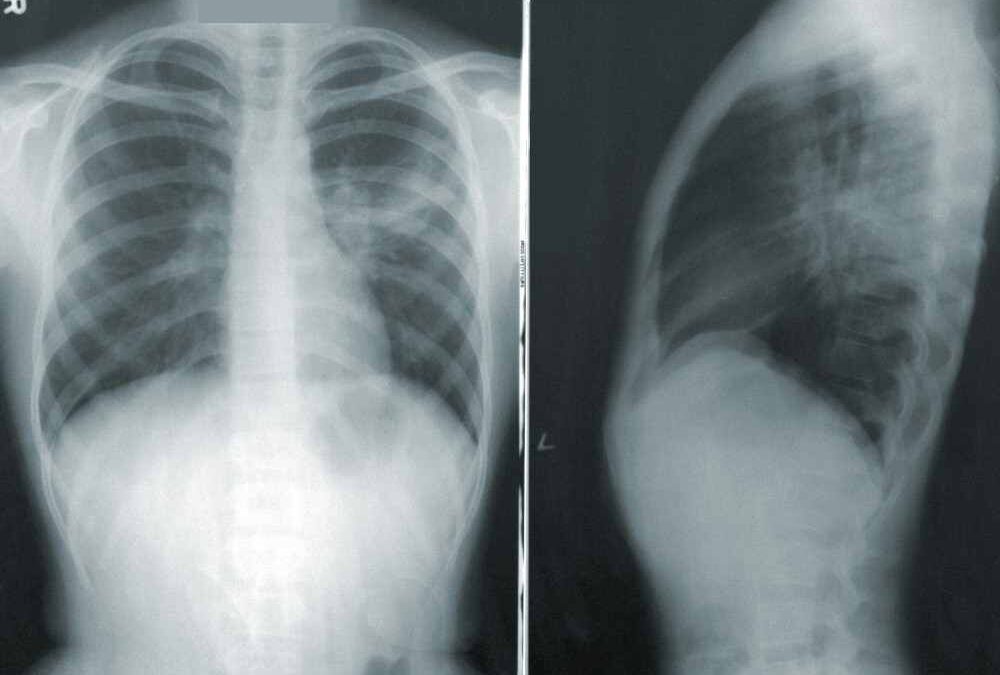

Cancer pulmonaire : Ne pas confondre avec infection pulmonaire et pneumopathie

Trop souvent, les symptômes précoces du cancer pulmonaire sont confondus avec d’autres affections respiratoires comme une simple infection pulmonaire ou une pneumopathie. Cette confusion peut retarder le diagnostic de plusieurs mois, période pendant laquelle la maladie progresse silencieusement.

Nodule pulmonaire témoignage

Roger, 62 ans : « J’ai d’abord pensé à une bronchite qui s’éternisait. Ce n’est qu’après trois mois que mon médecin m’a prescrit une radiographie. On m’a trouvé une opacité au poumon et un nodule pulmonaire sur le poumon droit. Le diagnostic précoce m’a sauvé, ça fait maintenant 12 ans et je profite pleinement de mes petits-enfants. »

Ces cancers se manifestent fréquemment par des plaques pleurales visibles à la radiographie bien avant les symptômes cliniques. Une surveillance régulière des personnes exposées permet parfois de détecter des anomalies très précocement, quand les chances de guérison sont maximales.